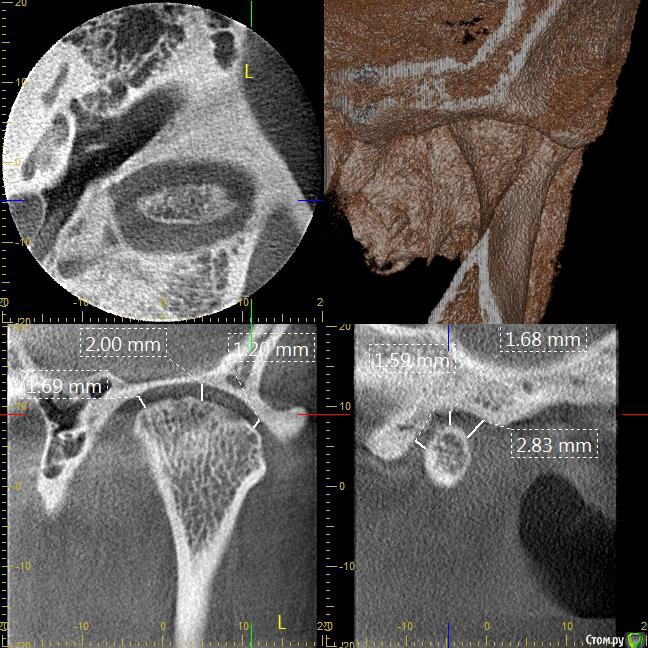

Мне 31 год. В детстве мне выбили верхний зуб 2-ку. Собираюсь лечиться брекетами, а потом вставлять имплант на место двойки. Но у меня есть еще проблеми с ВНЧС (с детства болит, хруст, щелчки), делала недавно КТ ВНЧС, диагноз артрит или артроз. Ходила к многим специалистам, все говорят разное. Надо ли проводить лечения капой моей дисфункции ВНЧС до установки брекетов или после установки брекетов?